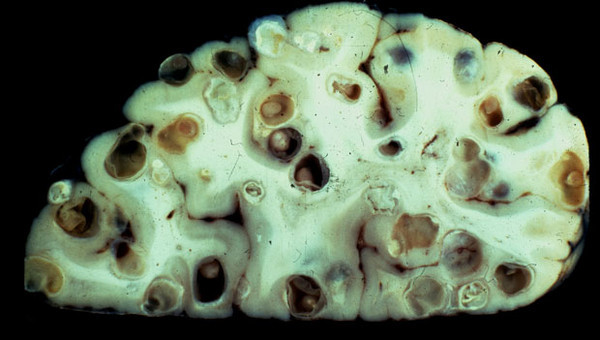

▼5.豬肉絛蟲(Taenia solium)。

▼這是一種很常見的寄生蟲,存在於沒有煮熟的豬肉內。牠雌雄同體,大概有7到13個子宮,150到200個睪丸,進入人體後會拼命繁殖。如果絛蟲卵囊進入腦部,成蟲會到處鑽孔,引發癲癇、失心瘋等可怕的症狀。